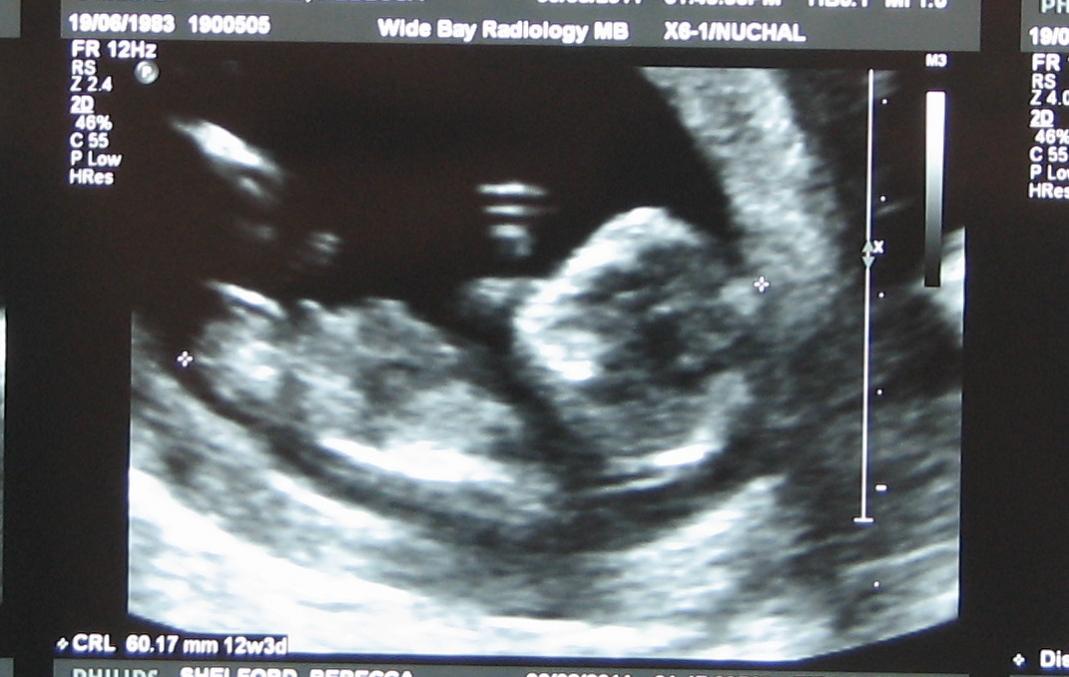

This is from 12 weeks 3 days. Thanks heaps to anyone who take a look & gives a guess.Attachment 594Attachment 593